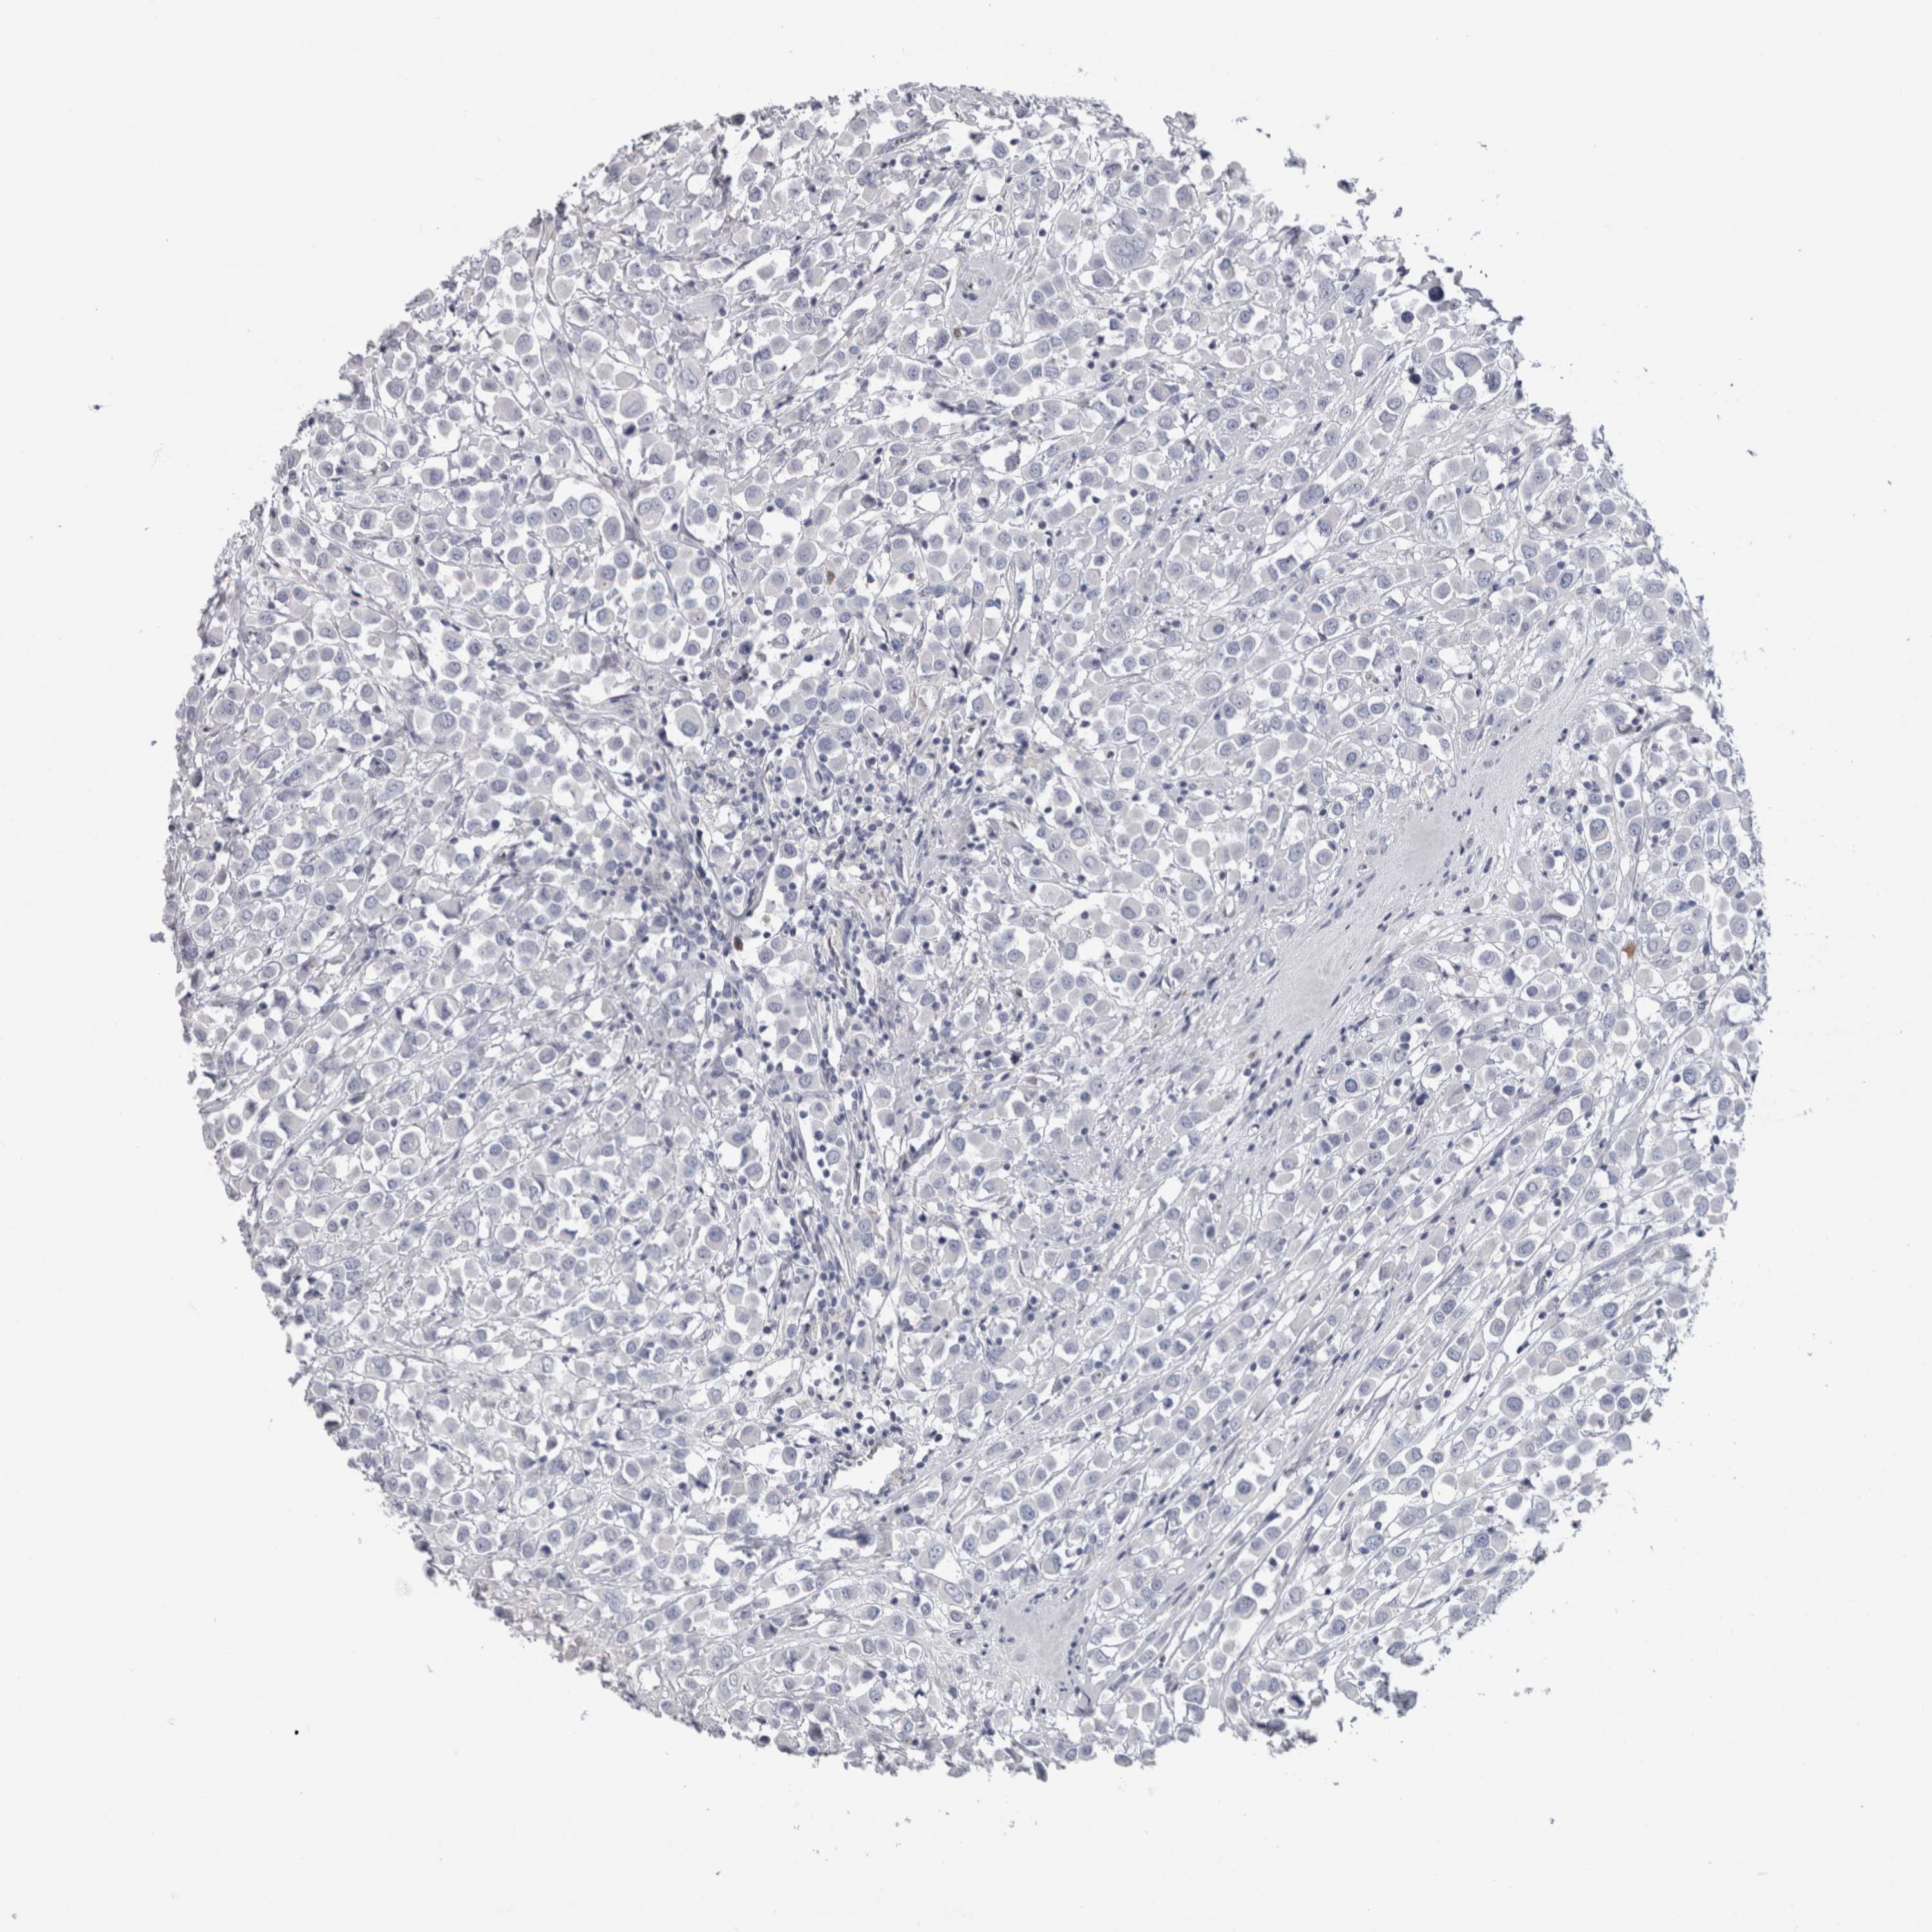

CANCER BREAST CANCER Show tissue menu

BRCA TCGA BRCA VALIDATION PROTEIN EXPRESSION

IL33 is not prognostic in Breast Invasive Carcinoma (TCGA)